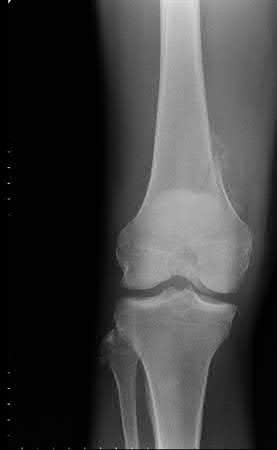

Buttress plating is most appropriate in which of the following clinical situations?

Figure A

Figure B

Figure C

Figure D

Figure E

Buttress plating is appropriate for a Shatzker Type I (see illustration C), as it can prevent collapse and axial deformity from shear or bending forces.

Figure B demonstrates an isolated medial femoral condyle fracture. Lateral locked plating is not an appropriate technique for this fracture.

The fracture shown in Figure B is an AO B type (partial articular fracture). This fracture is best treated with open reduction internal fixation through a medial approach, with lag screw and buttress plate fixation.

Figures A, C, D and E show supracondylar distal femur fractures that can be treated with ORIF with a fixed-angle device such as lateral locked plating.